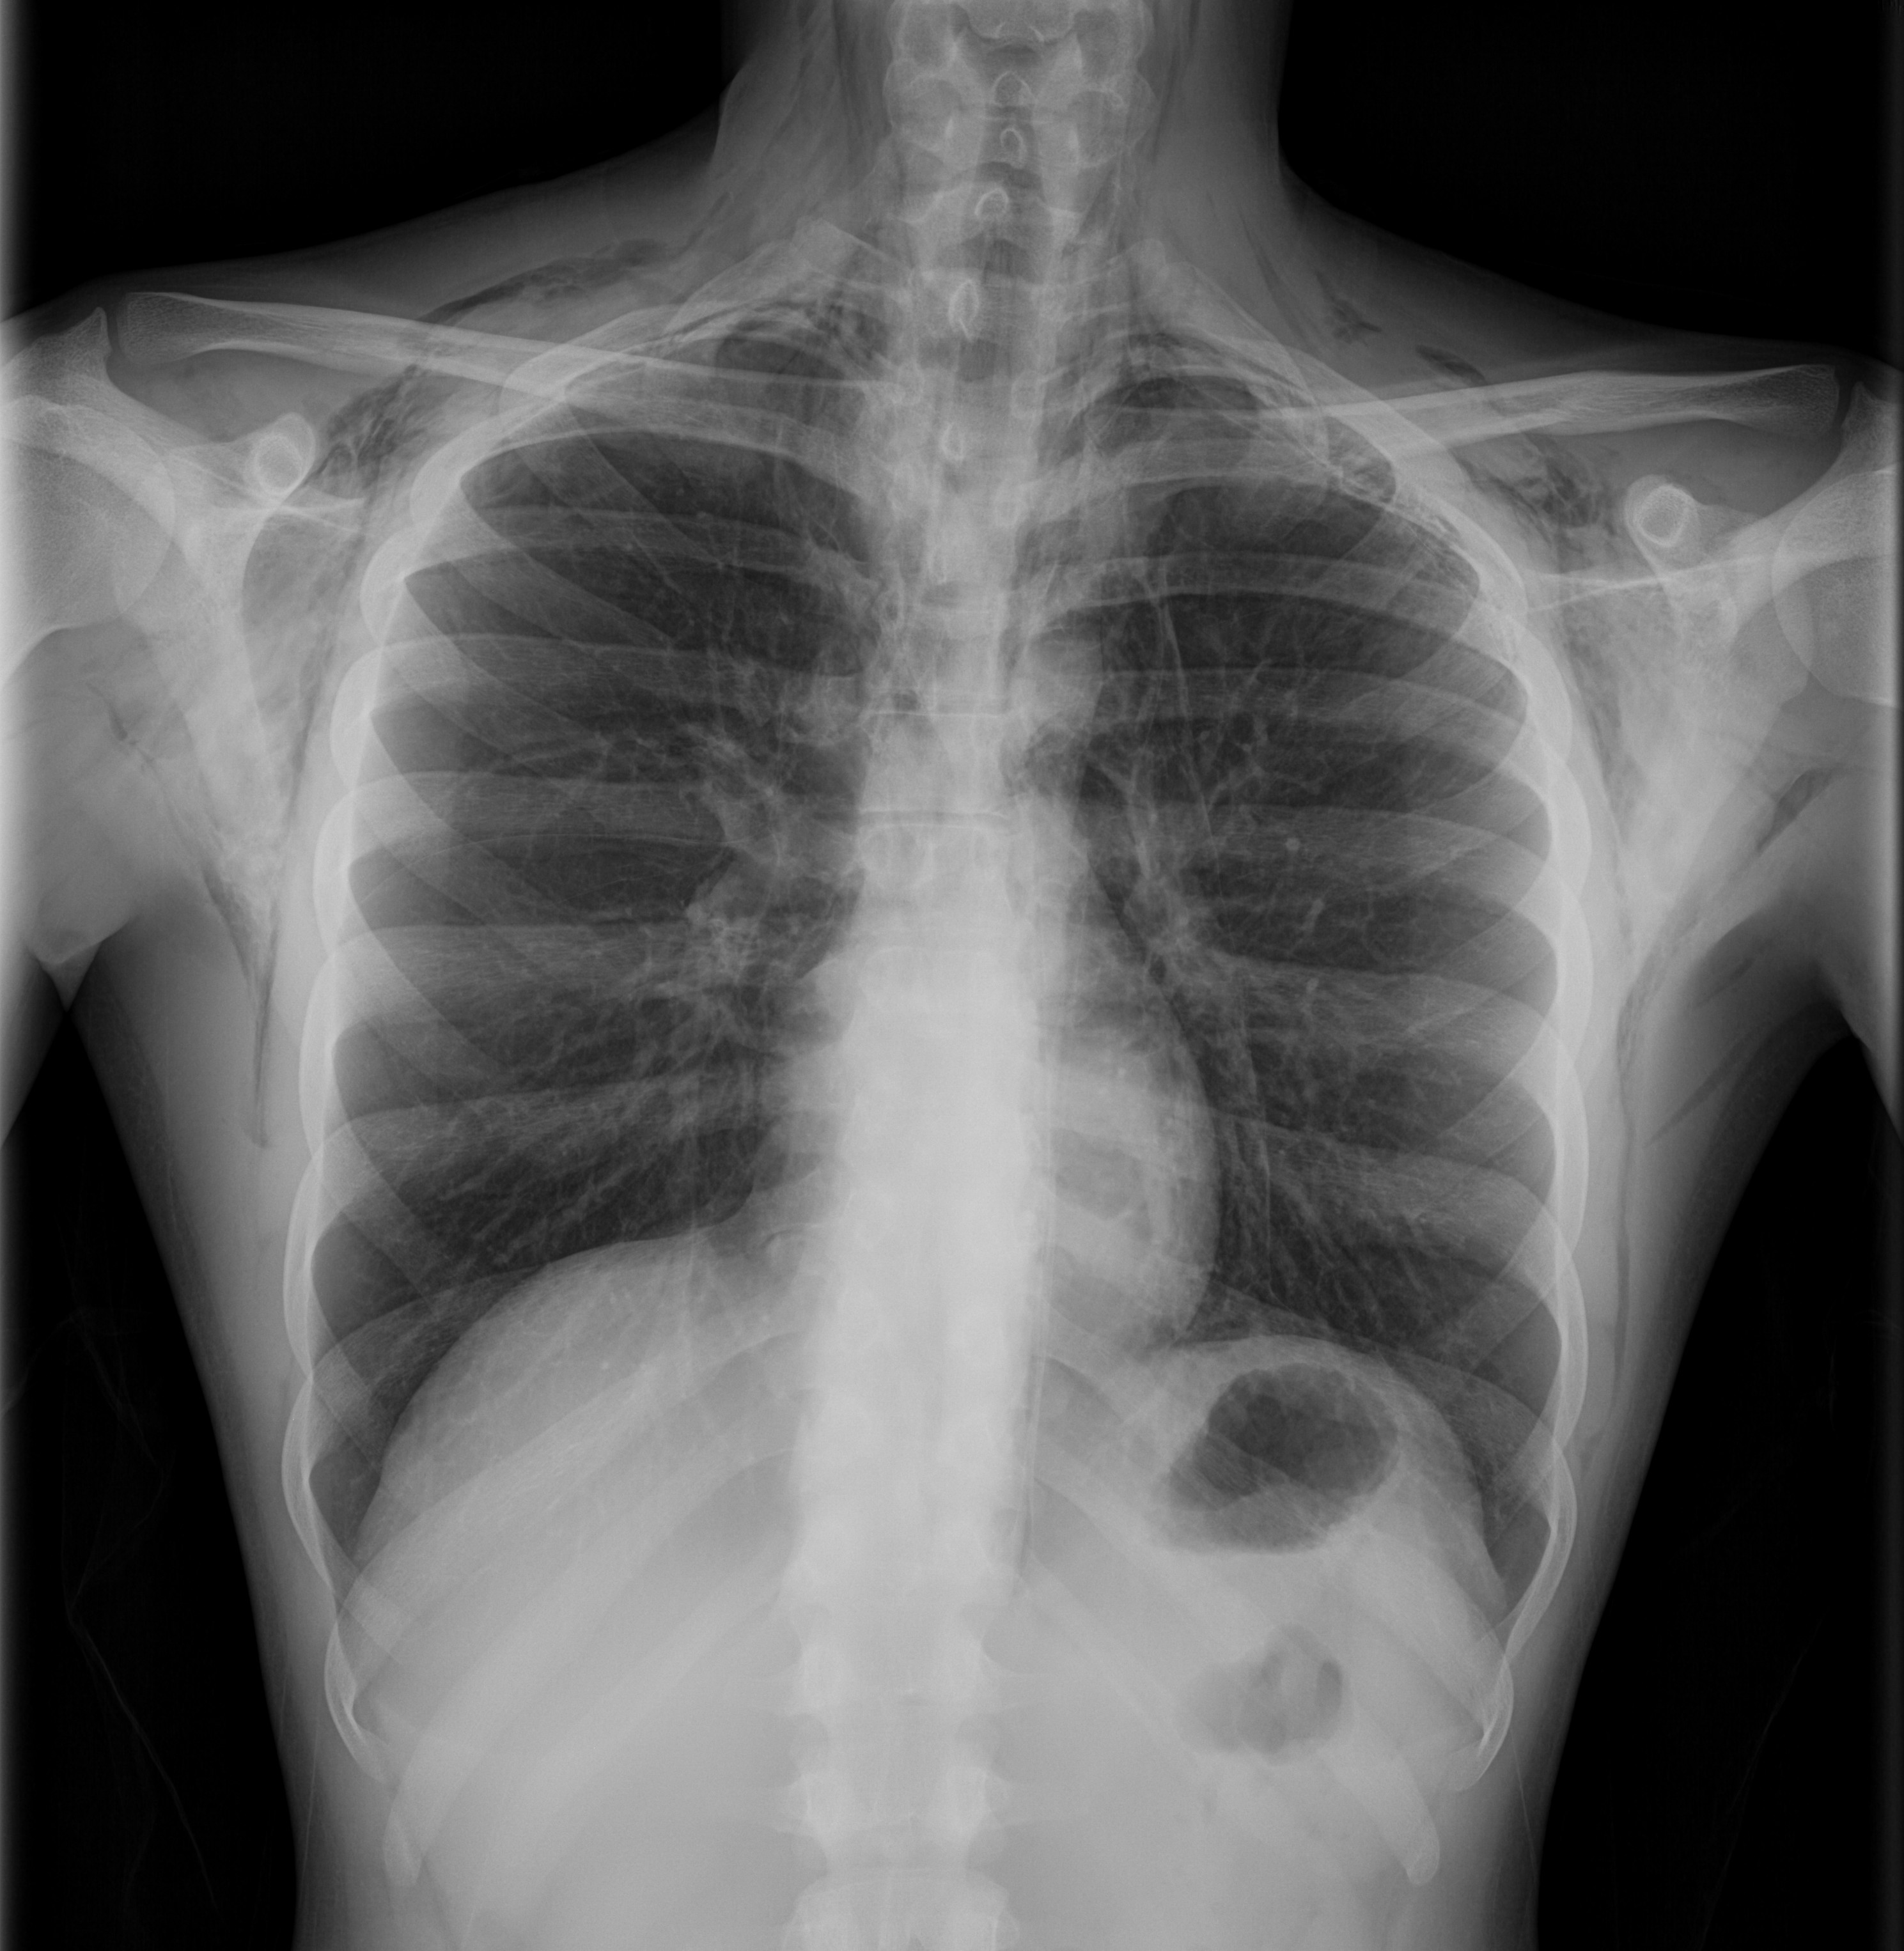

Radiografía de tórax: se confirma el enfisema subcutáneo y el neumotórax izquierdo, además se observa una línea vertical paracardíaca compatible con neumomediastino.

Neumomediastino espontáneo, enfisema subcutáneo y neumotórax izquierdo. Diagnóstico diferencial: rotura esofágica, rotura traqueal.